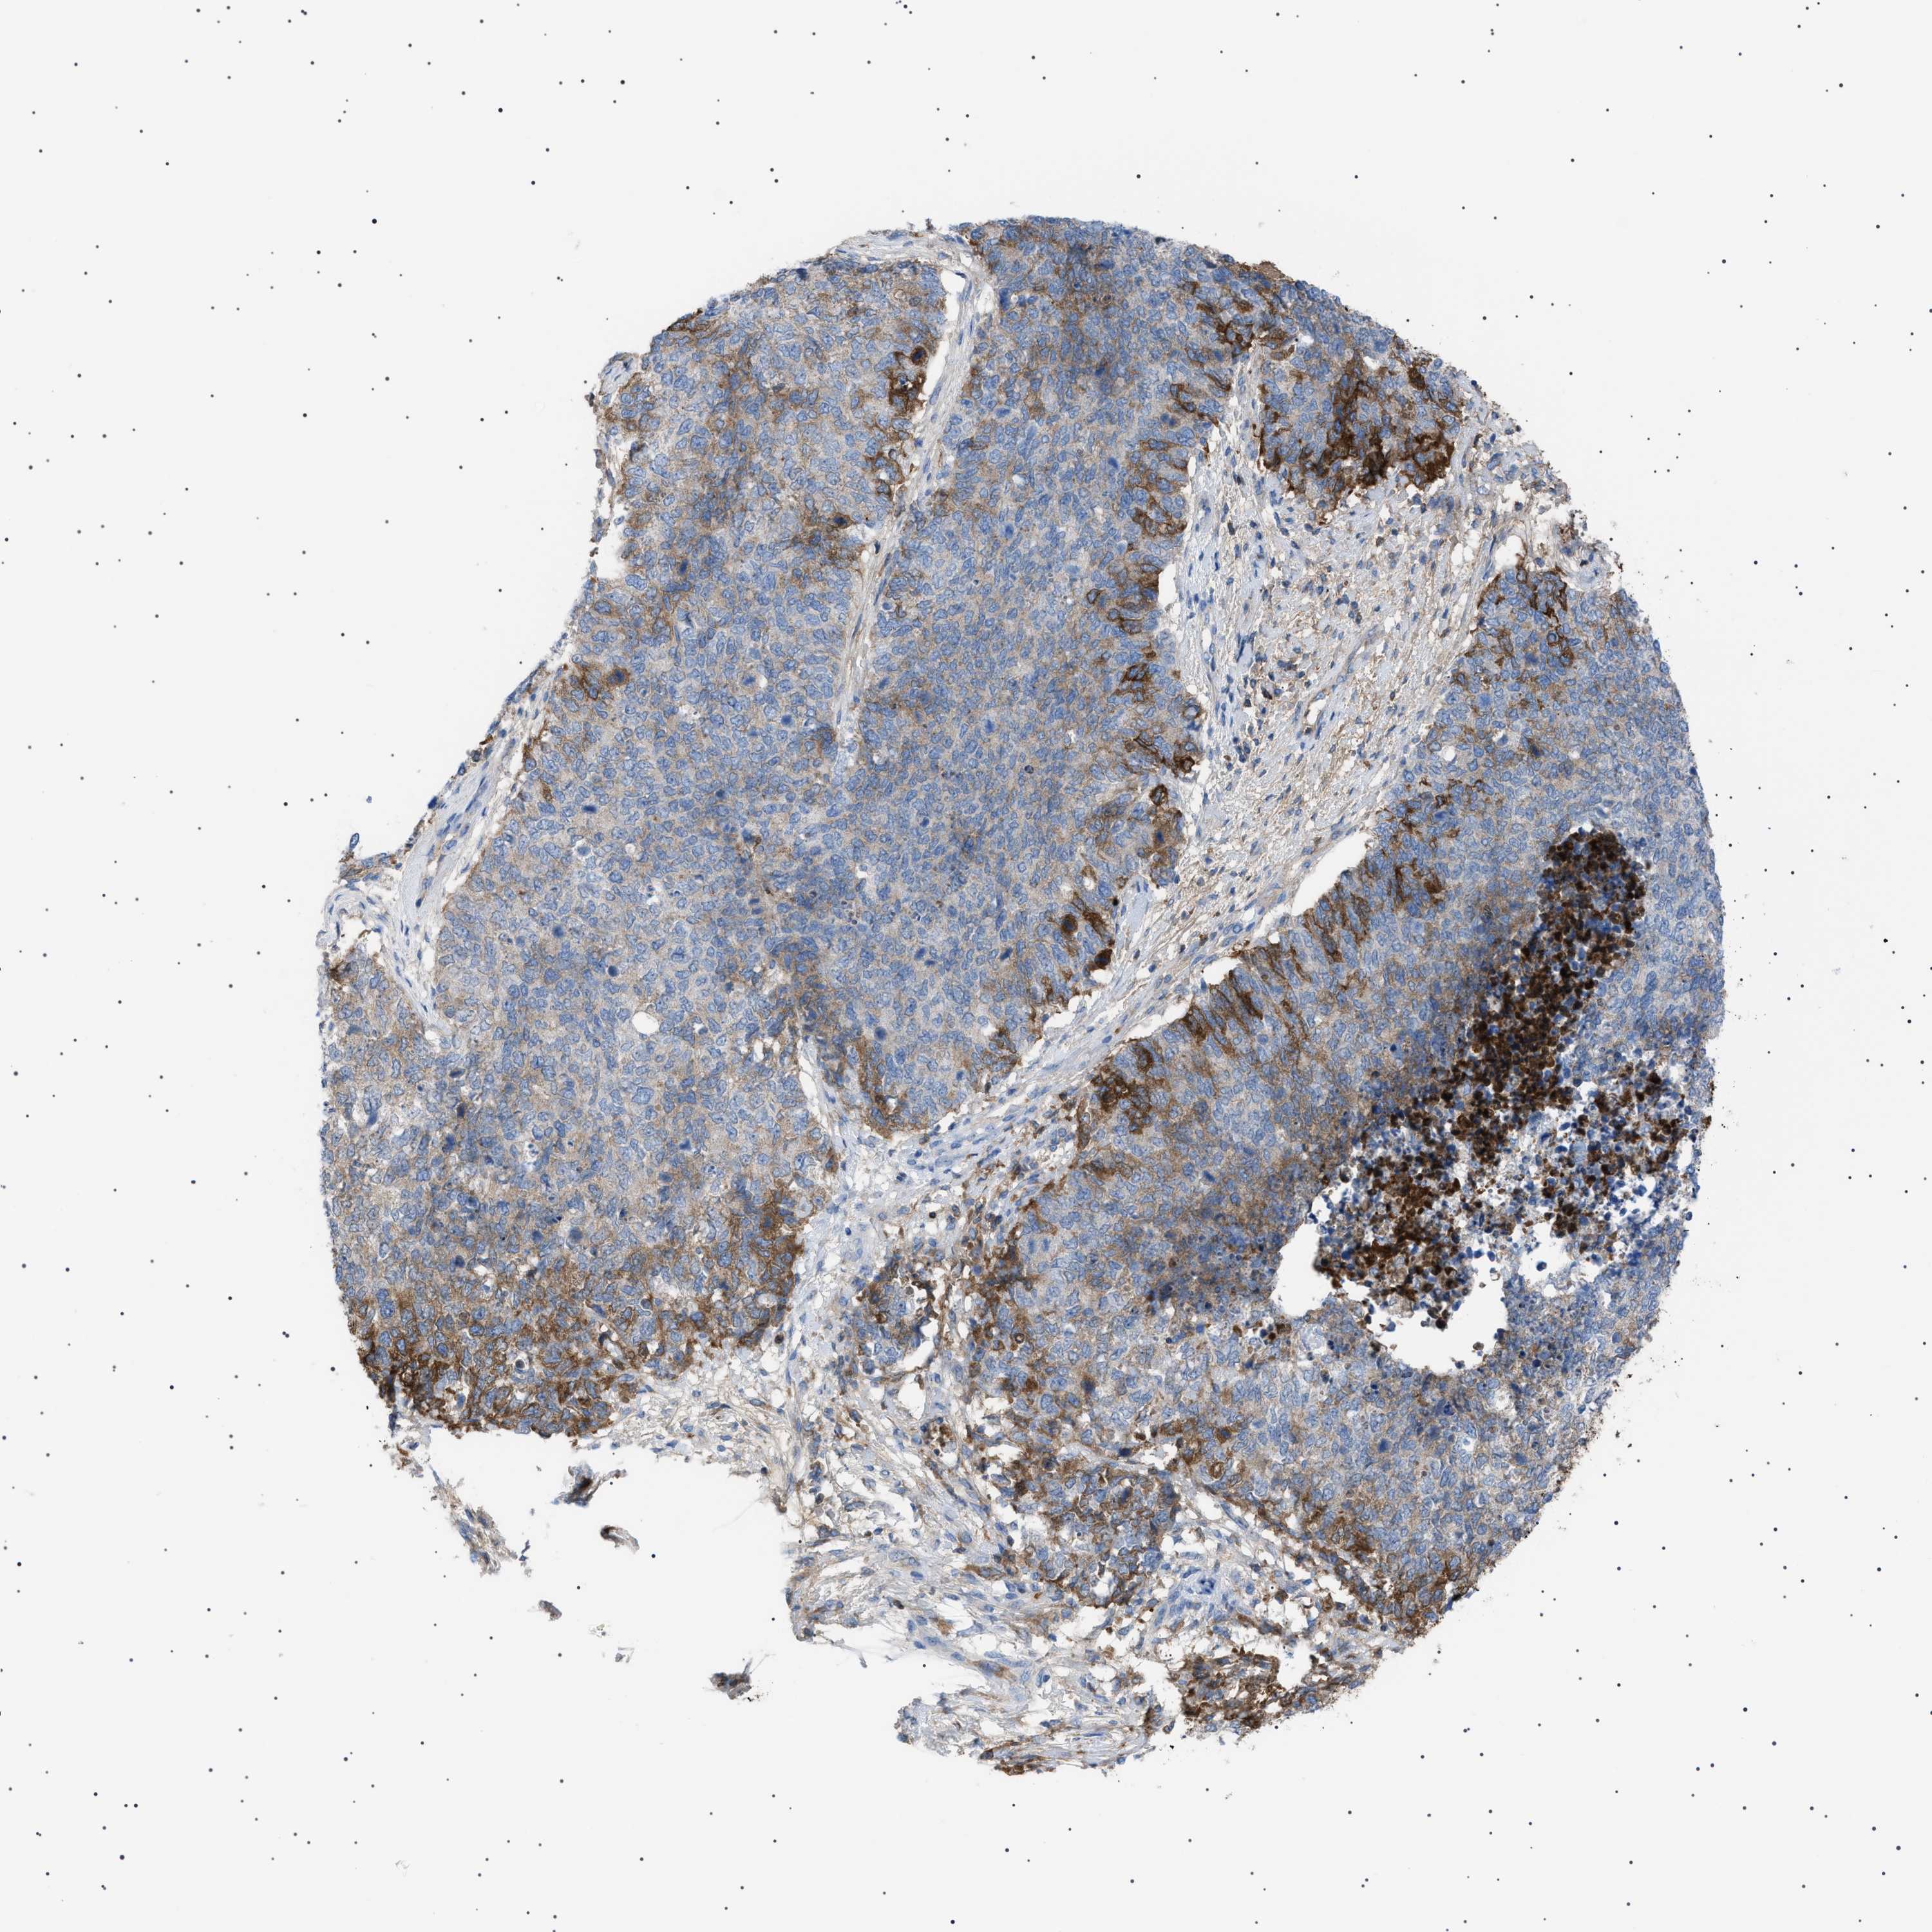

CERVICAL CANCER - Protein expressioni

A mouse-over function shows sample information and annotation data. Click on an image to view it in a full screen mode. Samples can be filtered based on level of antibody staining by selecting one or several of the following categories: high, medium, low and not detected. The assay and annotation is described here.

Note that samples used for immunohistochemistry by the Human Protein Atlas do not correspond to samples in the TCGA dataset.

Antibody stainingi

Antibody staining in the annotated cell types in the current human tissue is reported as not detected, low, medium, or high, based on conventional immunohistochemistry profiling in selected tissues. This score is based on the combination of the staining intensity and fraction of stained cells.

Each image is clickable and will lead to virtual microscopy that enables deeper exploration of all samples and also displays staining intensity scores, fraction scores and subcellular localization as well as patient and tissue information for each sample.

Antibody HPA060604

Antibody CAB016072